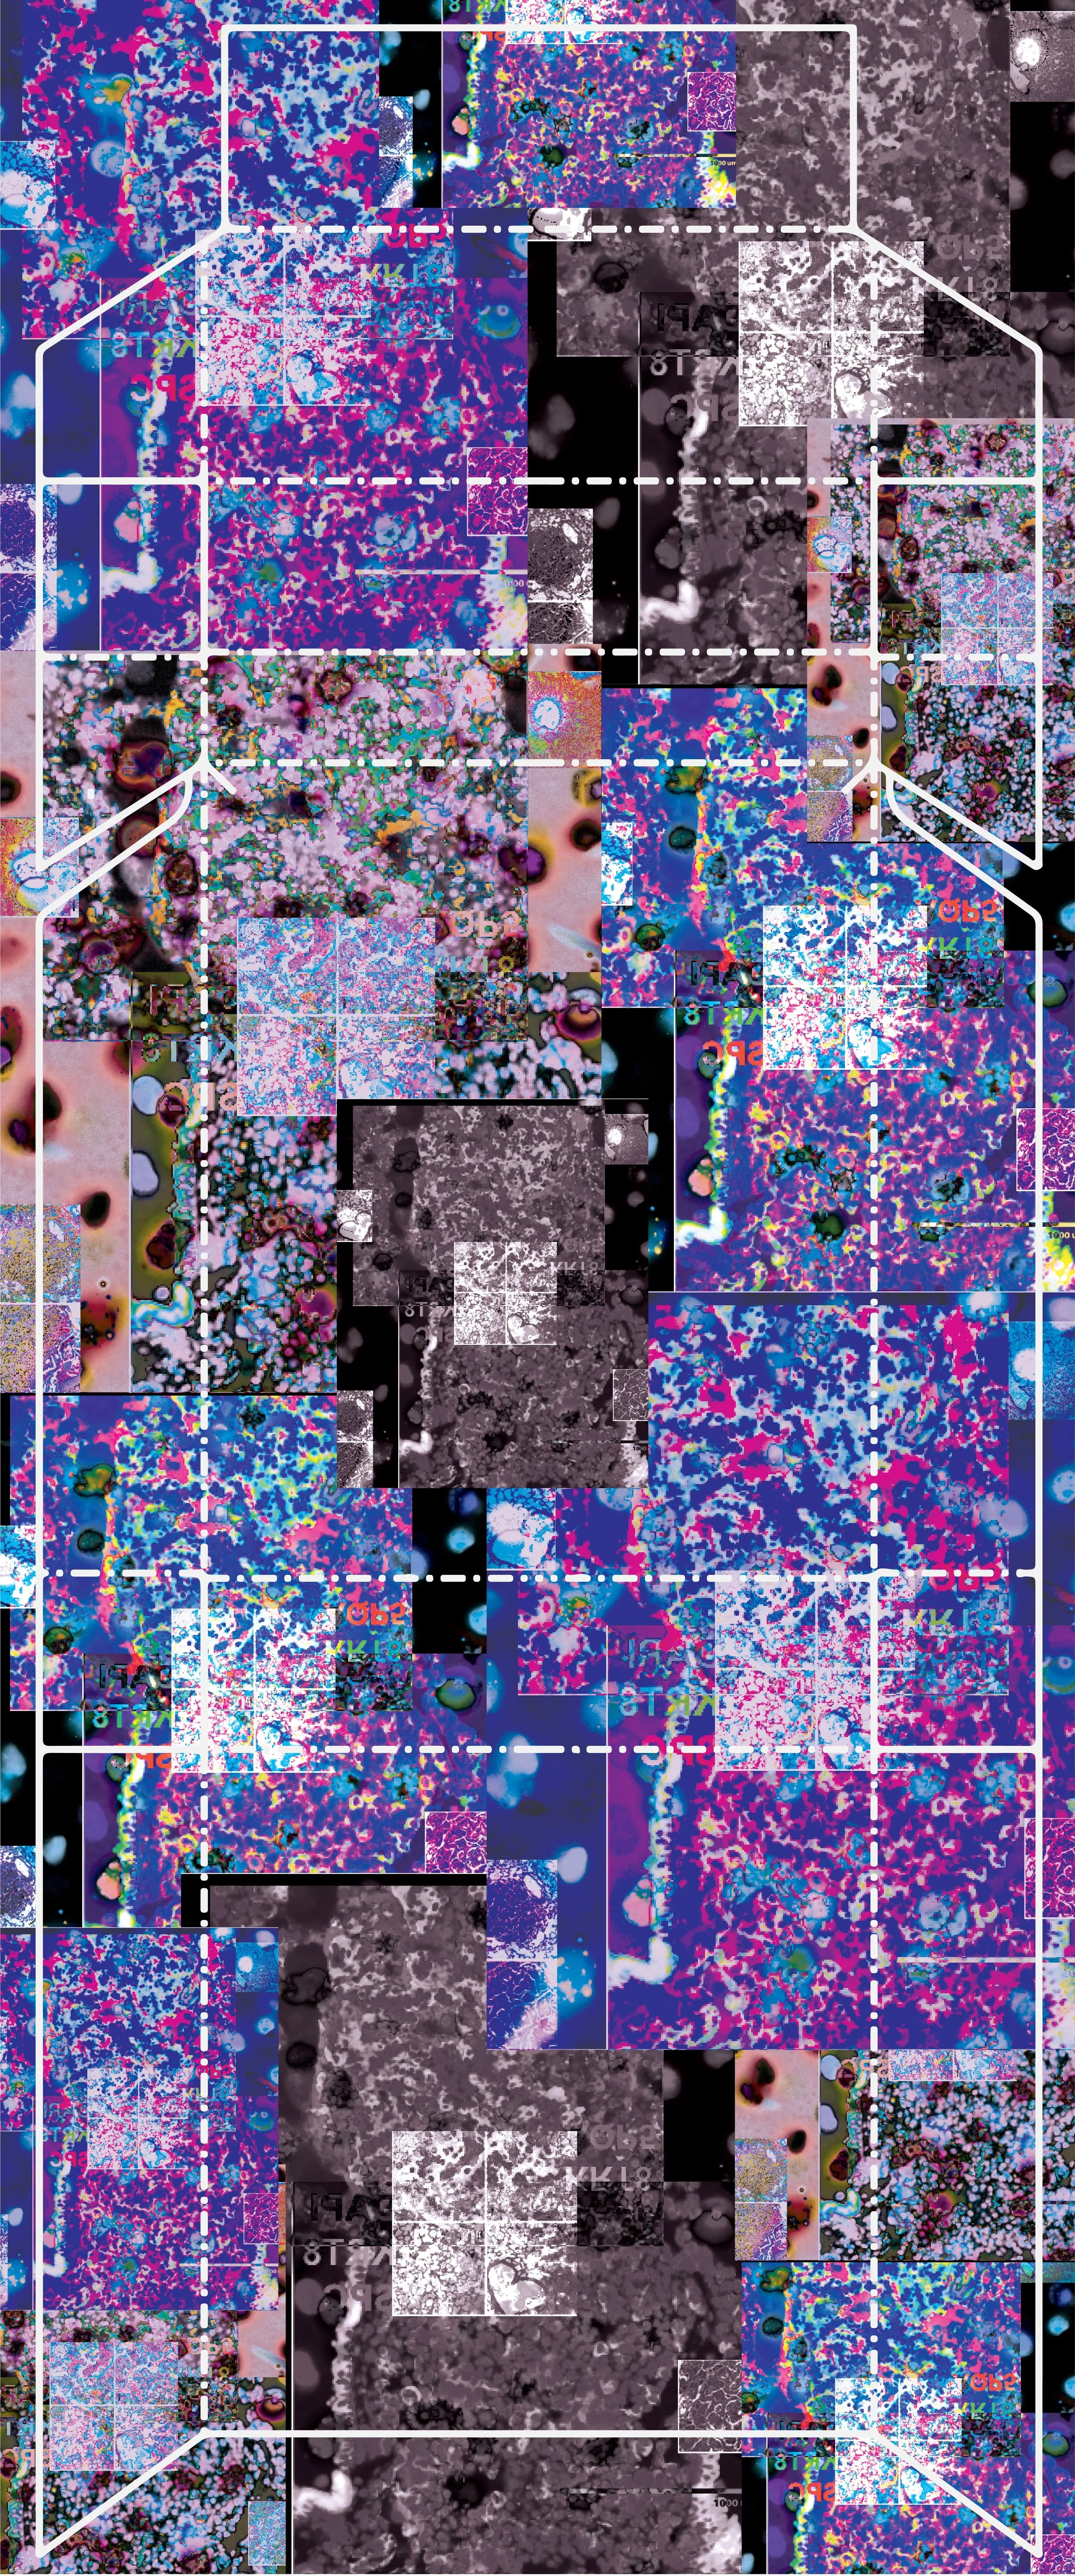

When working with Dr. Crystal Marconet and her research team, we wanted to highlight how lung cancer forms on a cellular level. Dr. Marconett and her team are researching how a specific gene, LNCC0261, can aid in treating lung cancer. Through the use of lung tumor scans, l was able to create a piece that not only shows how and why lung cancer affects the body but also ways it can be treated. Each of the cigarette boxes artwork shows different stages of lung cancer. The first shows an entirely healthy lung, the second a lung with cancer and being treated using the LNCCO261 gene, and the lasta lung with untreated lung cancer. The cigarette boxes themselves represent the main cause of lung cancer today: smoking.